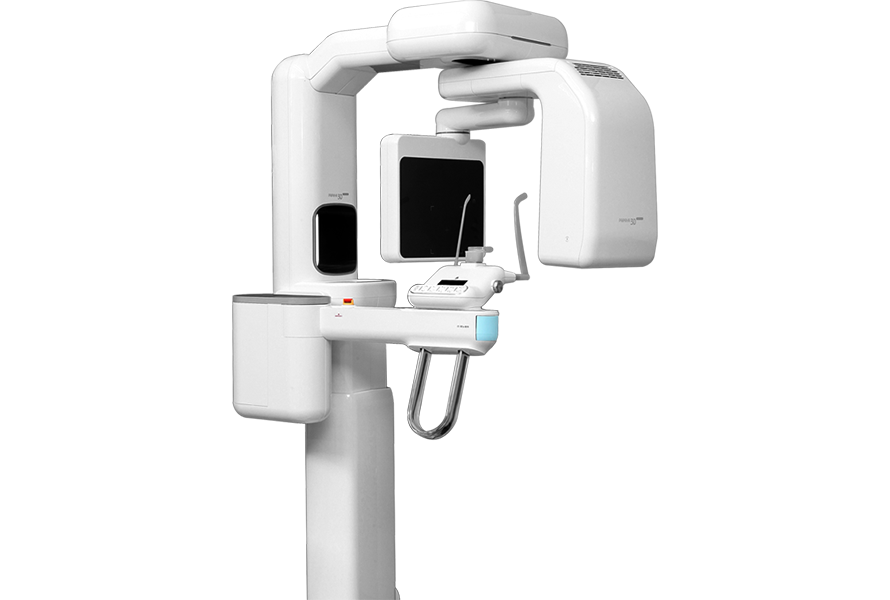

Превосходное качество изображения

Выберите самый большой сенсор

*23смХ14см и 23смХ24см

Удобный доступ

Обновленная и функциональная система позиционирования пациента для любых вариантов расположения аппарата.Обеспечивает удобство для всех пациентов и экономит ваше пространство.